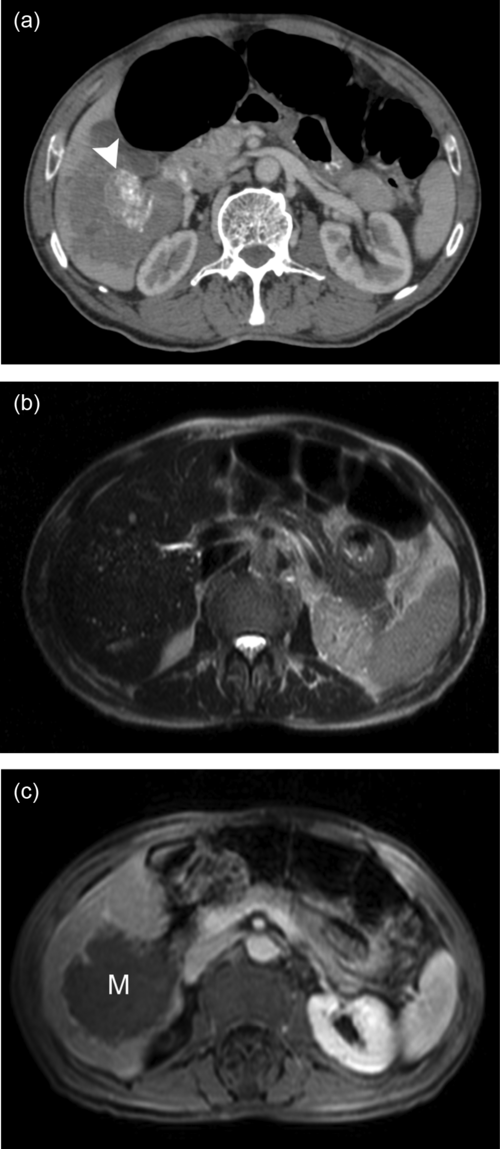

Liver phantom with multiple focal lesions including hemangioma, hepatocellular carcinoma, cyst, and metastasis for...